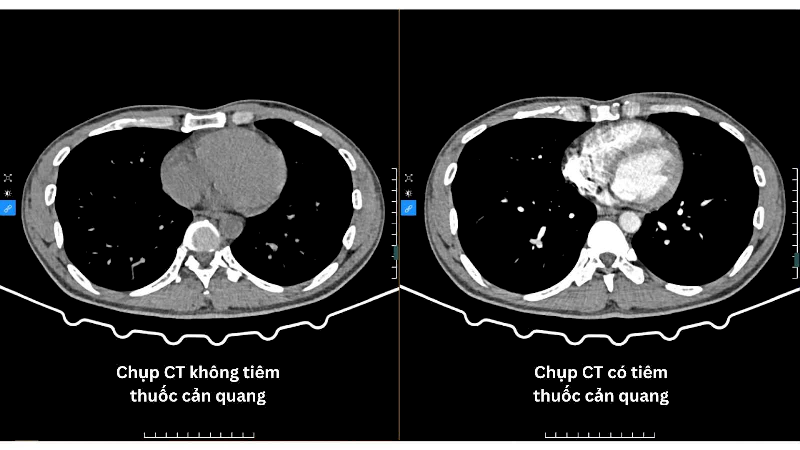

Chào bạn thân mến, Trên hành trình tìm hiểu và yêu thương cơ thể mình, chắc hẳn đôi lúc chúng ta sẽ gặp phải những thuật ngữ y khoa nghe có vẻ phức tạp, nhưng lại rất quan trọng cho sức khỏe. “Tiêm thuốc cản quang có tác dụng gì” là một trong những câu […]